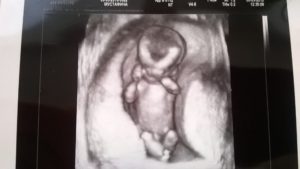

узи плода на 20 неделе

УЗИ плода в 20 недель беременности проводится рутинно в комплексе пренатальной диагностики.

В этот период акушер-гинеколог, проводящий УЗИ при беременности, может достаточно точно определить пол ребенка, вы сами сможете в этом удостовериться!

Ваш ребенок активно растет. При УЗИ плода в 20 недель беременности его длина составляет 19-20 см, а вес — около 400 граммов. При этом плоду еще достаточно места в его жилище, он свободно двигается, поворачивается, что можно увидеть при УЗИ плода в 20 недель беременности.

Информативным будет 3d 4d УЗИ плода при беременности, на котором доступны для просмотра лицевые структуры, спина, голова и т.д.

Если женщина еще не прошла второе плановое ультразвуковое исследование, то сейчас это нужно обязательно сделать. УЗИ на 20 неделе беременности позволит своевременно выявить возможные отклонения и патологии. Ведь некоторые из них можно скорректировать, если своевременно принять меры. Проведение УЗИ на 20 неделе беременности выполняют с целью:

- проведения фетометрии – это определение размеров различных частей тела плода;

- определения степени развития внутренних органов;

- выявить различные отклонения в развитии плода или в течение беременности. Например, низкое расположение плаценты, тонус матки или маловодие.

Кроме того, УЗИ в 20 недель позволяет родителям узнать, кто у них родится – сын или дочка. На этом сроке вероятность ошибок очень низкая, так как наружные половые органы малыша уже сформировались.

Совет! По желанию, на 20 неделе родители могут сделать УЗИ с эффектом 3D.Такой аппарат позволяет получить объемную цветную картину, и родители могут увидеть своего малыша и получить его первое «фото».